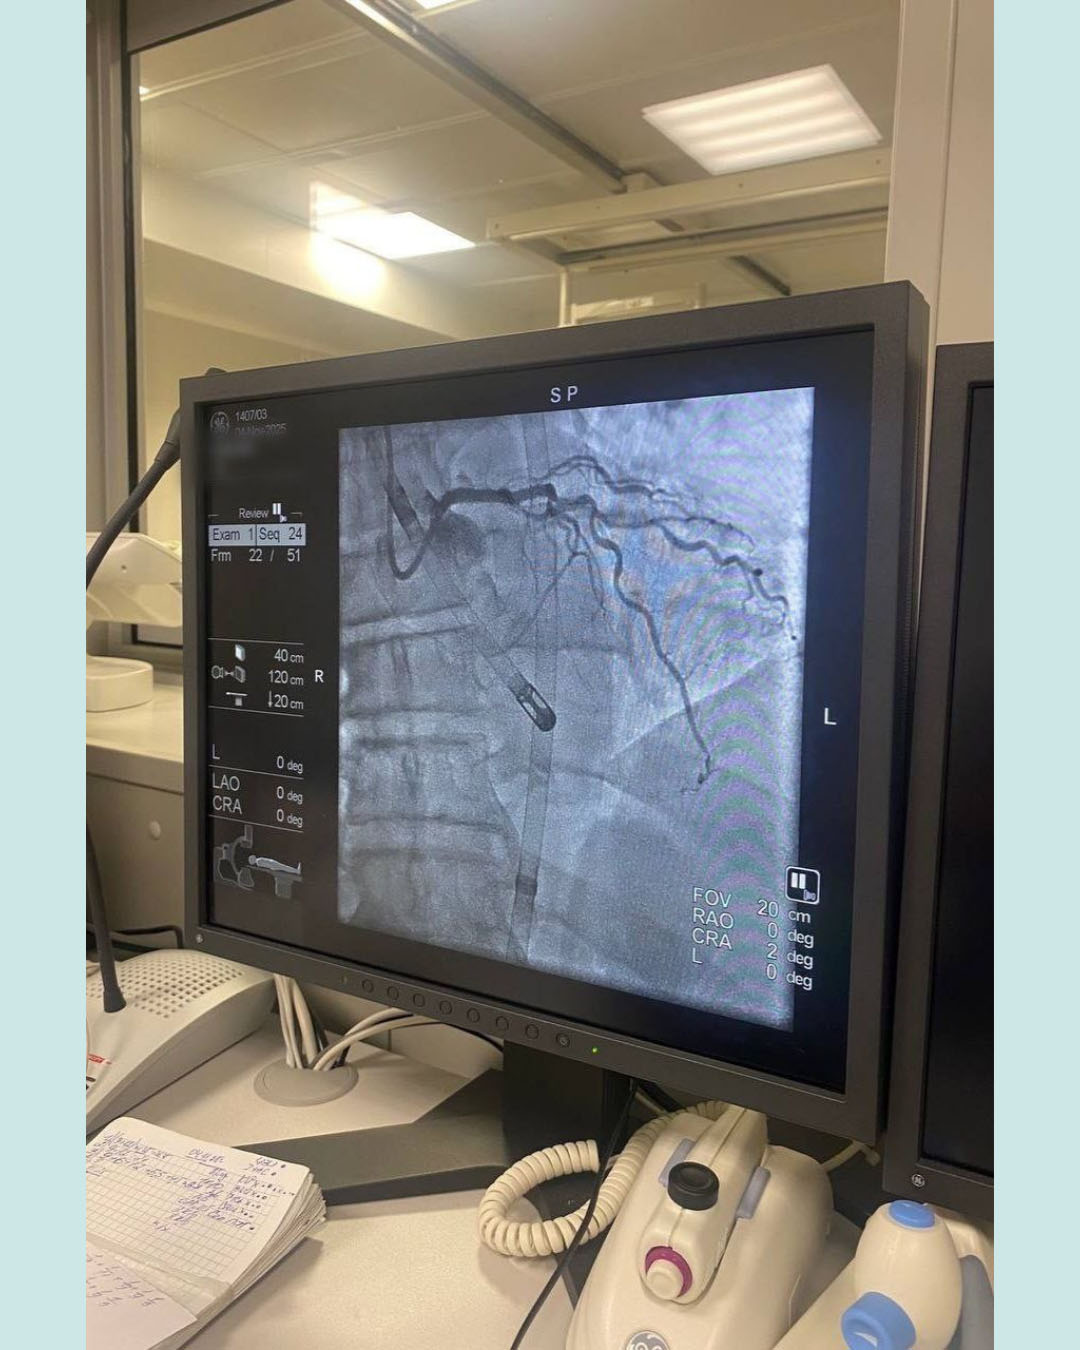

В последние годы медицина стремительно развивается, и кардиология – не исключение. Одним из примеров внедрения высоких технологий в практику стала успешная операция по стентированию ствола левой коронарной артерии у пациента с инфарктом миокарда, проведенная в Гомельском областном клиническом кардиоцентре с помощью уникальной технологии механической поддержки кровообращения – устройства PulseCath.

PulseCath – современное устройство, предназначенное для поддержки сердечного выброса. Оно позволяет обеспечить сердечный выброс до 2 литров в минуту. Одним из главных преимуществ системы является то, что она не требует общей анестезии и подключения к аппарату искусственного кровообращения. Это позволяет врачам проводить вмешательство в условиях ангиографического кабинета, что является важным фактором для благополучного исхода.